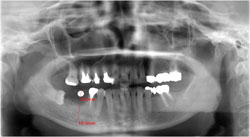

40歳代 女性 初診時のレントゲンです。

下の右側(画像では左下)の根だけ残っている歯を抜歯し、

インプラントを埋入する計画です。真横になっている親知らずはうまく抜歯して、

そのまま縦に再び埋入移植するようにします。